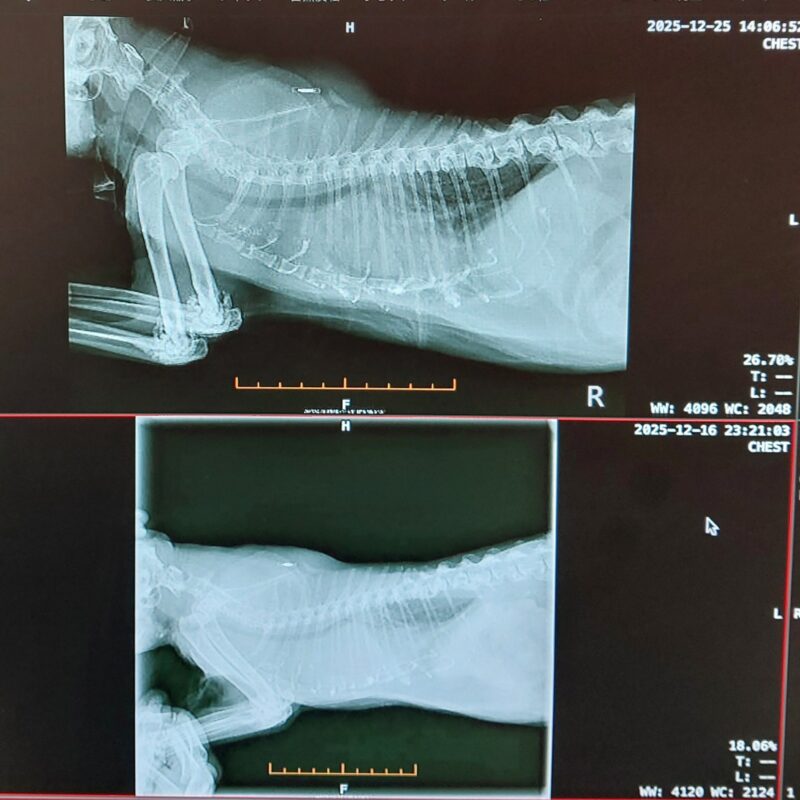

「胸部レントゲン検査結果」は、以下のレントゲン写真のとおり、いずれも上が2025年12月25日、下が2025年12月16日のものですが、下は真っ白でトモはとても苦しかったと思いますが、上は白くないところが写っていて、前回に比べ心臓や肺などの周りに胸水がそれほど貯まっていないように見えましたが、超音波検査では胸水が貯まっているということで、胸水抜去の処置をしていただきましたところ、以下のとおり80mlの胸水がトモの胸部に貯まっていました。

【以下獣医師の説明】 「胸部超音波検査」と「胸部レントゲン検査」の結果、前回(2025年12月16日)から9日で胸部の胸水がまた貯まっていたので、胸水を抜いたところ80mlあった。胸水が貯まる速度が早い。(上記に記載いたしました前回(2025年12月16日)以降の【トモの様子】の①について)本日も80mlの胸水が貯まっていたので、酸素室を導入しでいただいたのはとても良かった。本日から、心臓の薬(ピモベハート錠1.25mgを1日に半錠を2回)を始める。②についてはコメント特になし、③の足の裏に出来物は「床擦れ」であり、トゥルースリーパーではなく、「床擦れ防止」には「高反発マット」が良く、「ブレスエアー素材の犬猫用介護ベッド」があるのでそれを使用してはどうか。 との説明やアドバイスがありました。

また、レントゲン写真ですが、いつものことですが、トモの肘にモヤモヤしたものが写っていると思いますが、これがトモの「骨軟骨異形成症」です。手脚尻尾に軟膏のような瘤が出来て、手脚尻尾が痛くなり、ヨチヨチ歩きになってしまう病気です。この日は獣医師から「肋骨にも瘤が出来ていますね。」と言われました。「あちこち痛くてゴメンね、呼吸も苦しくてゴメンね…」と思いました😭。